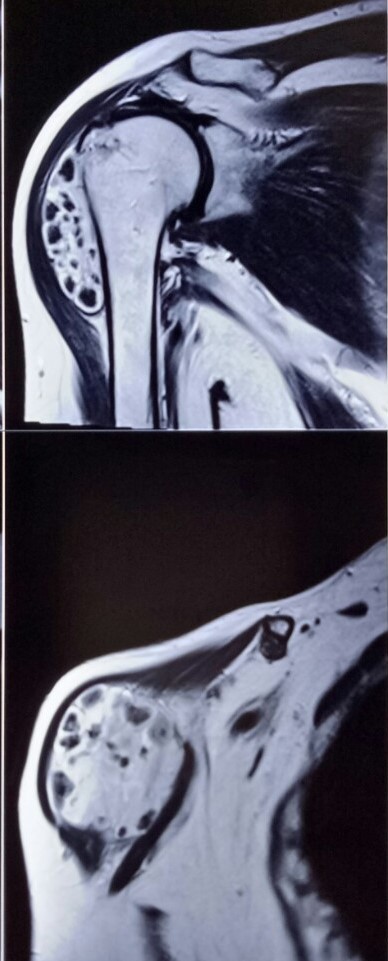

A 62 years old lady had a long-standing swelling over the right shoulder. MRI showed some adhesions with the upper end of the humerus. Was excised in toto. Biopsy report was hamartoma.